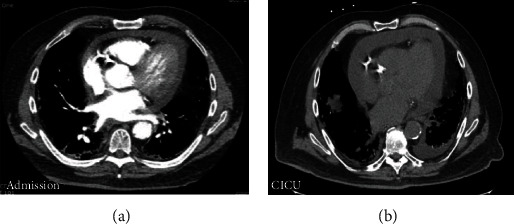

Purulent pericarditis is an extremely rare entity with only a few reported cases so far. This condition deserves prompt diagnosis because of its significant mortality rate if left untreated. A 76-year-old man with a past medical history of coronary artery disease (CAD) with percutaneous coronary intervention (PCI) to the left anterior descending artery (LAD) and right circumflex artery (RCA), ischemic cardiomyopathy with moderately reduced ejection fraction (EF 45-50%), peripheral artery disease (PAD), COVID-19 pneumonia complicated by fibrotic lung disease (on 3 liters of home oxygen), type-2 diabetes mellitus (T2DM), hypertension (HTN), hyperlipidemia (HLD), and chronic kidney disease (CKD) stage III presented with complaints of pleuritic chest pain and shortness of breath. On hospital day 1, he was afebrile and hemodynamically stable with physical exam remarkable for bibasilar crackles and dry gangrene of his right first toe. He developed progressive altered mental status, hypotension, oliguric renal failure, and respiratory distress on hospital day 6. On exam at this time, he had an elevated jugular venous distension (JVD) of 12-14 cm water, pericardial friction rub with decreased heart sounds, and orthopnea; all were consistent with cardiac tamponade clinically. An electrocardiogram (EKG) showed new ST elevations in leads I, II, and aVL with ST depression in aVR and V1 with only mild elevation in troponin I to 0.07 ng/mL. A transthoracic echocardiogram (TTE) was done on hospital day 7 and showed a moderate sized pericardial effusion with inferior vena cava (IVC) enlargement but no atrial collapse, ventricular collapse, IVC collapse, or respiratory variation in the mitral and tricuspid inflow velocities. Blood cultures grew methicillin-resistant Staphylococcus aureus (MRSA) on hospital day 6, and he was started on intravenous (IV) vancomycin. The differential diagnosis for his enlarging pericardial effusion included purulent pericarditis, uremic pericarditis, or hemorrhagic effusion. He had urgent diagnostic and therapeutic pericardiocentesis with removal of 350 milliliters of fluid. The pericardial fluid was cloudy, tan-brown with a gram stain showing gram-positive cocci in clusters and cultures growing MRSA, which confirmed the diagnosis of purulent pericarditis secondary to MRSA infection. After the pericardiocentesis, his blood pressure, respiratory distress, and renal failure improved. The source of the bacteremia was from osteomyelitis of his gangrenous, right toe with bone biopsy growing both MRSA and Streptococcus anginosus. He underwent toe amputation for definitive source control. He was discharged on hospital day 24 with a plan to complete 6 weeks of IV vancomycin.